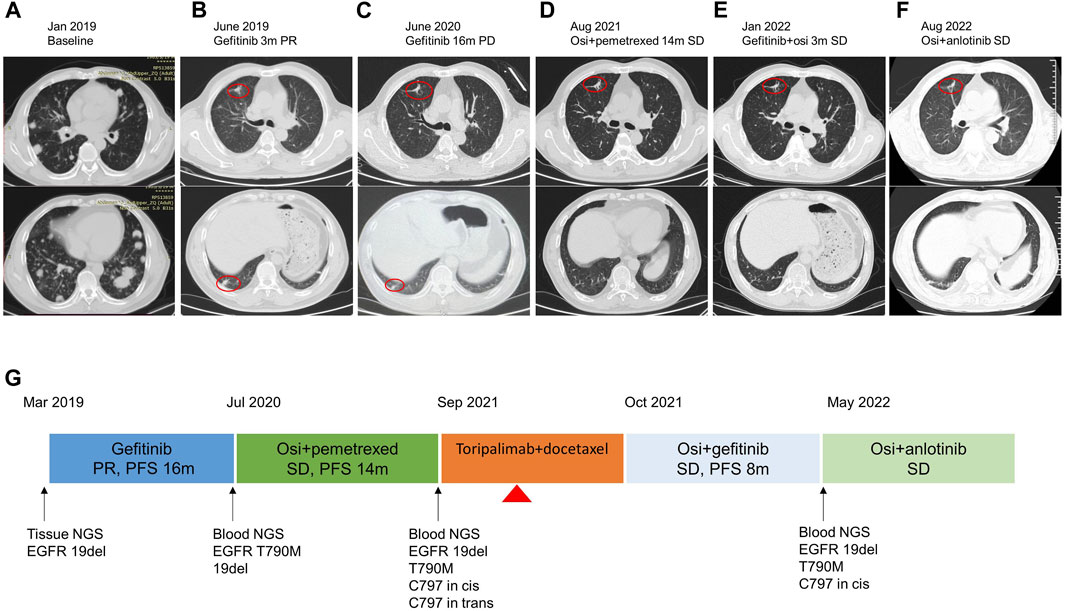

Primary Osseous Malignancies of the Spine。Thoracic spine metastases from lung cancer with incomplete。Frontiers | Stevens–Johnson syndrome induced by toripalimab。「WHO Classification of Tumours, 5th ed., Vol.5」著者: WHO Classification of Tumours Editorial Board出版社: WORLD HEALTH ORGANIZATIONISBN: 978-92-832-4506-3ページ数: 565pp.出版年: 2021年定価 :23.550円(税抜)裁断済みです。診察ができる vol.1 身体診察。Risk Factors for Poor Outcome after Palliative Surgery for。汚れはありません。